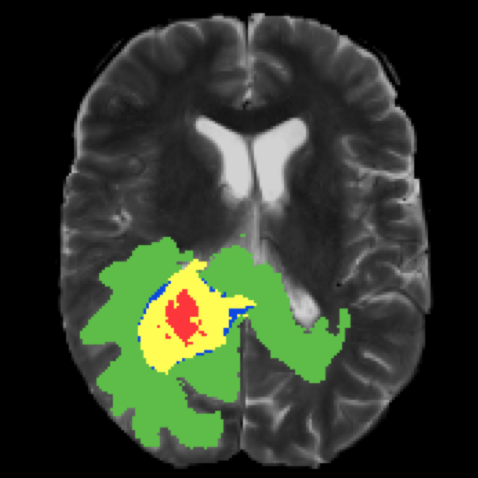

이러한 image segmentation은 의학사진, 자율주행, 위성이미지 분석 등의 다양한 분야에서 쓰인다.